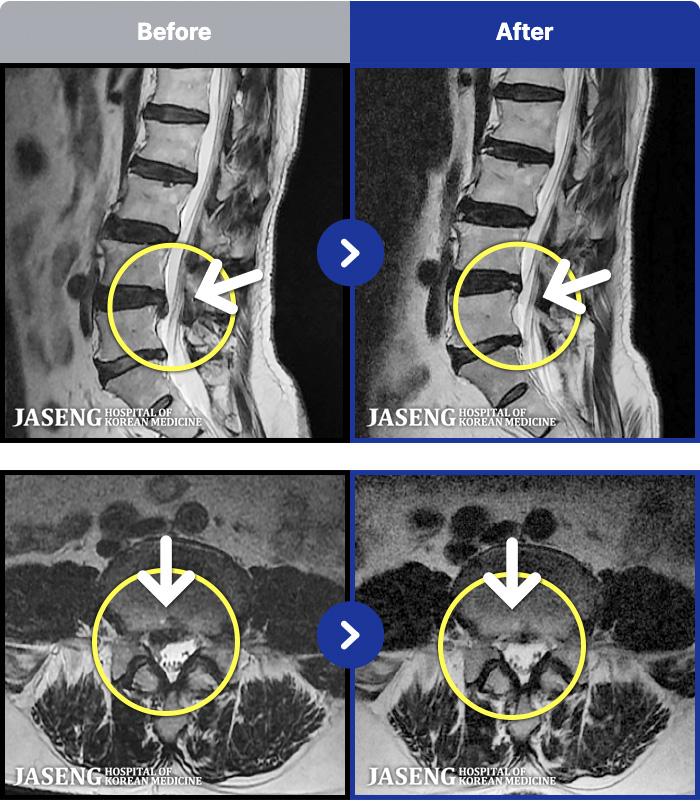

ȯںп Ǹ ǿ ԿǾ, ο ġ ۿ Ƿ ġḦ Ͻñ ٶϴ.